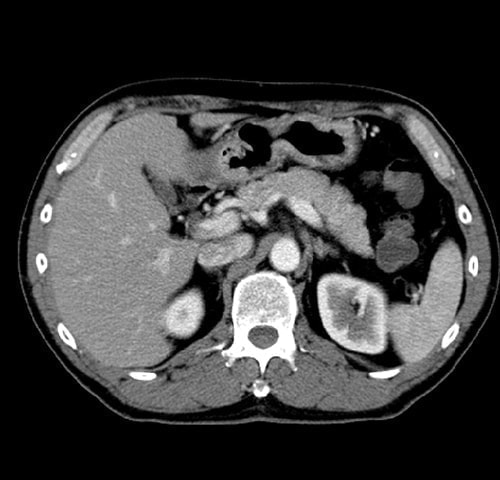

・ 腹部(肝臓・胆のう・ 膵臓・腎臓)病変

腹部